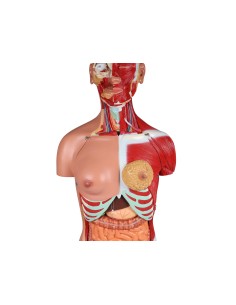

Scopri il Mondo dell’Anatomia con Modelli anatomici di Precisione

Modelli Anatomici Dettagliati per Ogni Necessità

Dal cranio in 22 parti con incastri magnetici ai modelli di colonna vertebrale, da quelli di articolazioni a quelli di cuore, ogni pezzo della nostra collezione è progettato per un’immersione totale nello studio dell’anatomia umana. I nostri modelli, realizzati tramite scansioni di ossa vere, garantiscono un’esperienza tattile autentica e una fedeltà di peso quasi identica agli originali.

Strumenti Didattici Innovativi per l’Educazione e la Pratica Medica

Essenziali per studenti e professionisti, i nostri modelli anatomici sono strumenti didattici che permettono di osservare le strutture anatomiche con precisione, eliminando la necessità di dissezioni o studi invasivi. Sono inoltre utili per spiegare ai pazienti le patologie, rendendo la comunicazione più efficace e risparmiando tempo prezioso.